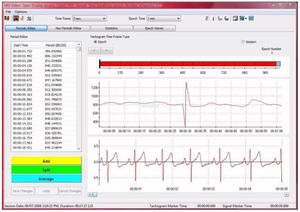

... de análisis de datos que antes sólo estaban disponibles en paquetes de software muy especializados, como el software CardioPro de Thought Technology. CardioPro Infiniti es un módulo ...